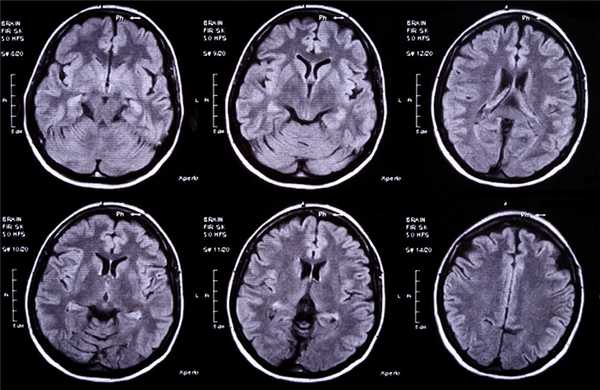

Для того чтобы провести точную диагностику места расположения абсцесса мозга и мозжечка, проводят компьютерную и магнитно-резонансную томографию головного мозга. При проведении компьютерной томографии выявляется тонкая, гладкая стенка абсцесса, которая имеет правильные контуры. Магнитно-резонансная томография позволяет также определить капсулу абсцесса. Если нет возможности провести вышеперечисленные виды исследования, можно провести пневмоэнцефалографию или радиоизотопную сцинтиграфию головного мозга.

Точность диагностирования с помощью КТ головного мозга зависит от стадии формирования абсцесса. На ранних стадиях заболевания диагностика затруднена. На этапе раннего энцефалита (1-3 сутки) КТ определяет зону сниженной плотности неправильной формы. Введенное контрастное вещество накапливается неравномерно, преимущественно периферических отделах очага, реже в центре.

На более поздних этапах энцефалита контуры очага приобретают ровные округлые очертания. Контрастное вещество распределяется равномерно, по всей периферии очага; плотность центральной зоны очага при этом не меняется. Однако на повторной КТ (через 30-40 минут) определяется диффузия контраста в центр капсулы, а также наличие его и в периферической зоне, что не характерно для злокачественных новообразований.

Инкапсулированный абсцесс мозга на КТ имеет вид округлого объемного образования с четкими ровными контурами повышенной плотности (фиброзная капсула). В центре капсулы зона пониженной плотности (гной), по периферии видна зона отека. Введенное контрастное вещество накапливается в виде кольца (по контуру фиброзной капсулы) с небольшой прилежащей зоной глиоза.

На повторной КТ (через 30-40 минут) контрастное вещество не определяется. При исследовании результатов компьютерной томографии следует учесть, что противовоспалительные препараты (глюкокортикостероиды, салицилаты) в значительной степени влияют на скопление контраста в энцефалитическом очаге.

МРТ головного мозга — более точный метод диагностирования. При проведении МРТ на первых стадиях формирования абсцесса мозга (1-9 сутки) энцефалитический очаг выглядит: на Т1-взвешенных изображениях — гипоинтенсивным, на Т2-взвешенных изображениях — гиперинтенсивным. МРТ на поздней (капсулированной) стадии абсцесса головного мозга: на Т1-взвешенных изображениях абсцесс выглядит, как зона пониженного сигнала в центре и на периферии (в зоне отека), а по контуру капсулы сигнал гиперинтенсивный. На Т2-взвешенных изображениях центр абсцесса изо- или гипоинтенсивный, в периферической зоне (зоне отека) гиперинтенсивный. Контур капсулы четко очерчен.